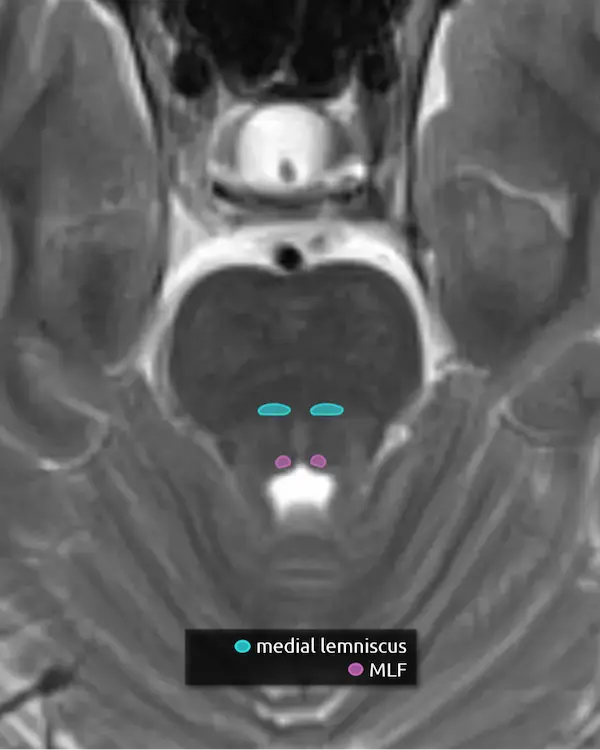

6. Medial longitudinal fasciculus (MLF)

The MLF is an ascending and descending pathway responsible for coordinating eye movements. It connects all of the cranial nerve nuclei that innervate the extraocular muscles (CN III, IV, and VI) as well as the vestibulocochlear nuclei (CN VIII). The MLF spans the entire brainstem, however lesions producing visual symptoms will probably be in the midbrain or pons.

There are characteristic syndromes that result from damage to the MLF, most commonly internuclear ophthalmoplegia (INO) or INO-plus syndromes. A common clinical scenario is a patient with multiple sclerosis who develops a demyelinating lesion along the MLF in the midbrain or pons and presents with bilateral INO.

5. Medial lemniscus

The medial lemniscus is an ascending sensory pathway that spans the entire brainstem, originating at the nucleus gracilis and cuneatus (see level 5) in the medulla and ending at the primary sensory nucleus of the thalamus: the ventral posterolateral nucleus (VPL). It begins medially in the medulla and becomes more lateral at the level of the midbrain, located in close proximity to the substantia nigra. It is responsible for vibration sensation, fine touch, and proprioception.

Lesions involving the medial lemniscus may cause contralateral loss of vibration sensation and joint position sensation on physical exam with symptoms of numbness and paresthesias.